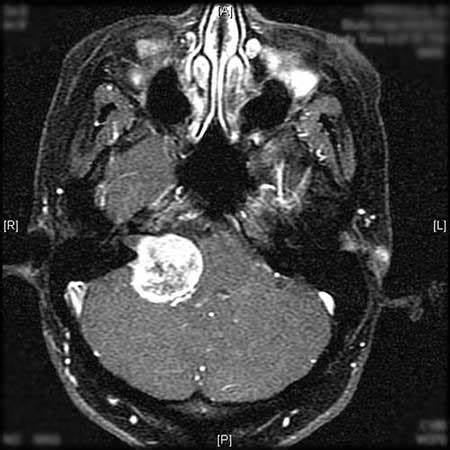

听神经瘤是一种非癌性肿瘤,它有两个“身份”:虽然听神经瘤通常由脑外科医生治疗,但实际上听神经瘤并不是从脑细胞中生长出来的。听神经瘤并不是这种肿瘤的正确名称。一般来说,这是前庭神经鞘瘤,因为肿瘤生长在前庭神经上,前庭神经是连接平衡系统和大脑的导线,位于桥小脑角。

对于听神经瘤的手术治疗,主要包括传统手术和显微外科手术,传统手术是采用肉眼观察,有较大的限制,一般已经被有实力的医院所摒弃。目前前沿手术是显微外科手术,显微外科手术通过多种技术实现外科手术三维可视化和准确化,应用手术显微镜或辅助其他手术设备可以达到更好的光照条件、更清晰的手术视野及更合适的放大倍数,效果明显优于传统的裸眼手术,这些是显微外科手术的优势所在。

听神经瘤手术切除虽然为优选方式,但是也有其限制之处,在手术切除中,会有较高概率损失面神经和听神经。当患者面神经被损伤,会出现面瘫的现象,而听神经被损伤,则可能长期耳聋。所以目前听神经瘤手术面神经的保存、听力的保存是当前神经外科医生所面临的的较大挑战。

巴特朗菲教授在显微外科手术三维可视化和准确化下,结合神经导航、神经电生理检测、DTI、术中核磁等多种前沿设备,只要患者之前没有听力损失,对3cm以下的听神经瘤,巴特朗菲教授不仅能做到完整切除,且不损伤听力,不造成面瘫,对于具有较大挑战性的3cm以上听神经瘤,他在完整切除的同时且尽可能地使听力保留,大概率以上的概率不会面瘫。